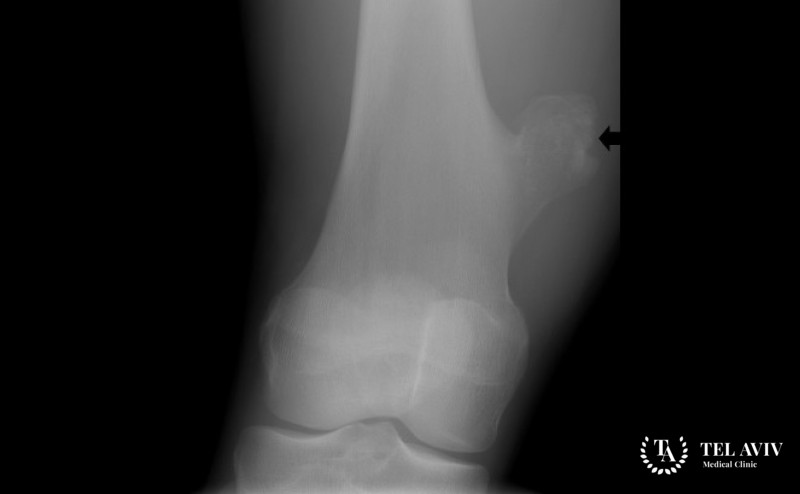

Остеохондромы – костные новообразования доброкачественного типа. Относятся к распространенным патологиям. Они представляют собой выросты на костных тканях, ощутимые при пальпации. Причина – аномалии в энхондральном окостенении. Образование обладает костной основой, ее накрывает хрящевая оболочка. Толщина оболочки небольшая.

Интенсивность увеличения патологии идентичная скорости роста скелета. После завершения процесса роста скелетного основания, останавливается развитие остеохондромы. На основании выроста может образоваться вторичная хондросаркома, хондрома. В данной ситуации хрящевое покрытие костного образования значительно разрастается. Возникает риск превращения доброкачественной опухоли в злокачественный процесс.

Опухолевое образование небольшой размерности не вызывает симптомов у ребенка. Болевой синдром отсутствует. Зачастую патология выявляется в случайном порядке. Характерные признаки патологии:

- На костной ткани формируется шишка;

- Крупная остеохондрома оказывает компрессию на мышечные, нервные ткани, сухожилия. Функционал конечностей нарушается, формируется стойкий болевой синдром;

- Сумка над остеохондромой приводит к спонтанным переломам, развитию ложных аневризм, тромбозов в подколенных венах;

- При пальпации патология проявляется в виде уплотнения. Подвижность отсутствует. Изменения кожных покровов на костным наростом не отмечаются.